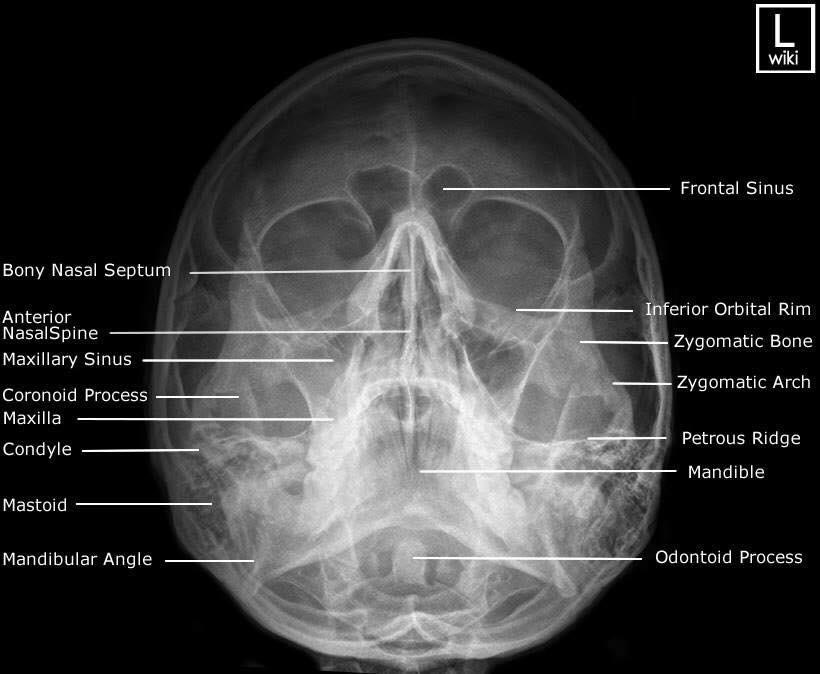

Las radiografías, generalmente llamadas rayos X, producen imágenes como sombras de huesos y ciertos órganos y tejidos. Las radiografías son muy buenas para detectar problemas óseos. Pueden mostrar algunos órganos y tejidos blandos; sin embargo, la MRI y la CT suelen crear mejores imágenes de los mismos. Aun así, las radiografías son rápidas, fáciles de obtener y menos costosas que los otros estudios, por lo que se pueden usar para obtener información rápidamente.

Un tubo especial dentro de la máquina de rayos X emite un haz de radiación controlada. Los tejidos del cuerpo absorben o bloquean la radiación en diferentes grados. Los tejidos densos como los huesos bloquean la mayor parte de la radiación, pero los tejidos blandos, como la grasa o los músculos, bloquean menos radiación. Después de pasar por el cuerpo, el haz alcanza una pieza de un fragmento de película o un detector especial. Los tejidos que bloquean altas cantidades de radiación, como los huesos, aparecen como áreas blancas en un fondo negro. Los tejidos blandos bloquean menos radiación y aparecen en tonos de gris. Los órganos que contienen principalmente aire (como los pulmones) aparecen en negro. Los tumores son por lo general más densos que el tejido que los rodea, por lo que suelen verse en tonos grises más claros.